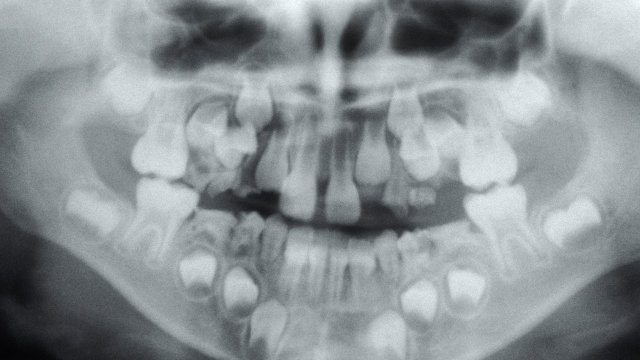

아이의 치아 배열과 턱 성장을 함께 고려하는 성장기 교정

턱뼈의 성장 방향과 속도를 고려해, 치아 발달을 유도하는 교정으로,

우리 아이의 치아는 아직 완성되지 않았습니다.

위아래 턱의 불균형 성장으로 인한 교정

턱의 성장 방향을 유도하여 불균형을 해결하고, 부정교합을 예방하는 교정을 시행합니다.

치아의 공간이 부족한 경우

영구치가 맹출될 공간이 부족한 경우, 미리 공간을 만들어 영구치가 자연스럽게 나올수 있도록 도와주는 교정입니다.

혼합치열기 교정

유치의 탈락과 영구치의 맹출이 진행될 때 시행하는 교정으로 치아 교체 시기와 맞물린 시기이기 때문에 의료진의 성장 예측과 경험이 중요한 교정입니다.